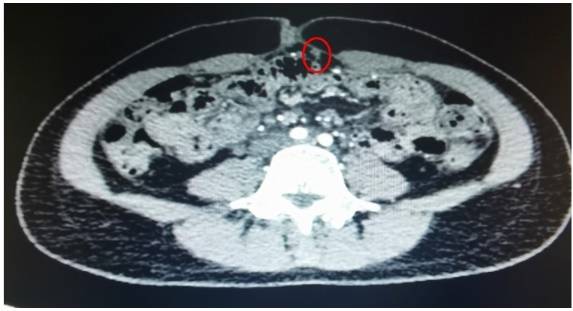

◈ 2022年8月26日,患者突发腹部疼痛。急诊行腹部CT检查提示:盆腔见较大不规则形混杂密度影,与双侧附件及邻近肠管、右侧髂血管分界不清,最大层面约13.4cm×11.8cm,其内密度不均,可见片状高密度影及钙化密度影,病变周围似见稍高密度包膜影。左上腹部小肠旁见肿块影,与局部肠管分界不清,局部肠管走行紊乱,管壁似欠连续,腹腔内见较多液体密度影及游离气体密度影。网膜略增厚。

2022年8月26日 腹部CT

◈ 检查结论:1、盆腔占位病变,对比2022-07-15片似变大,建议进一步检查。2、腹腔游离气体、考虑消化道穿孔,左上腹部小肠旁占位性病变,3、腹腔积液,对比前片积液量减少,网膜略增厚。

◈ 诊断为消化道穿孔,急诊行剖腹探查术。术中见近端小肠肿物破裂穿孔。盆腔囊实混杂肿物,周围境界关系不清,但仍可姑息切除,且需切除一侧附件,与家属充分沟通后,行小肠肿物切除术,盆腔肿物切除术,单侧附件切除术,大网膜切除术(R2切除)。